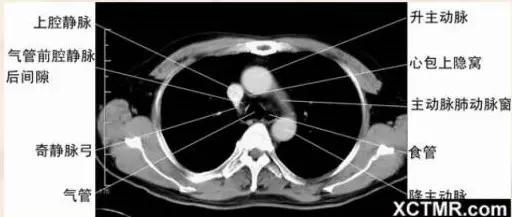

主肺动脉窗层面